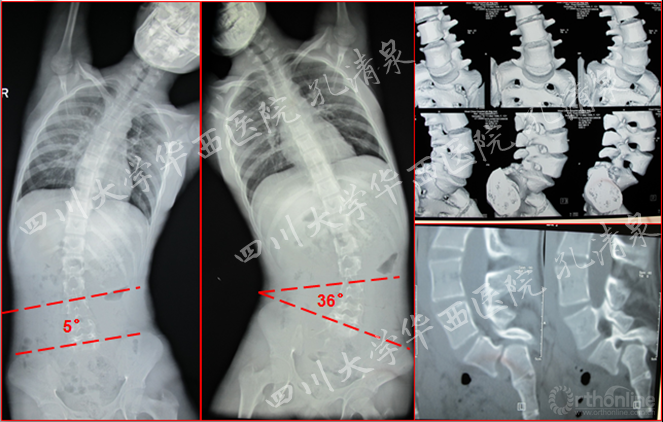

图2 侧弯的左右bending位摄片及腰骶部CT的矢状面重建及表面重建

图8 腰椎正位像上示多节段腰椎右侧横突骨折,腰骶部侧凸,CT矢状面重建示腰5椎IV°滑脱,腰5骶1椎间盘完好,骶1前上缘骨骺向前滑移

如果基于上述理论,我们的第一例病例应该接受腰椎滑脱和侧凸的同期手术。但我们经过深入分析,腰椎滑脱是有症状的,具有手术指针,脊柱侧凸虽然角度较大(颈7-胸3侧凸Cobb角16°,胸3-腰2侧凸Cobb角50°,腰3-腰5侧凸Cobb角35°),但其柔韧性较好(减轻位上胸椎侧凸12°腰椎侧凸5°),并且没有影像学上椎体旋转的证据.所以我们认为,这是一种非结构的继发性侧凸的可能性大,其处理不能等同于特发性脊柱侧凸,所以应该尽量减少固定融合节段,动态观察其自发侧凸矫正的潜能。